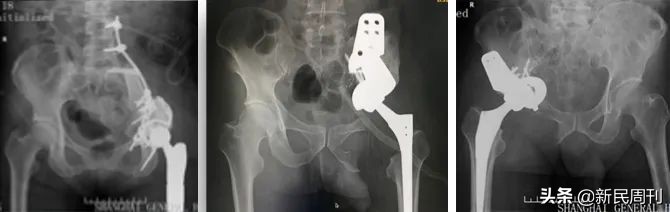

骨盆、骶骨肿瘤切除是一种风险大、难度高的手术。闯过了手术本身的风险,医生还要解决手术后骨盆的缺损怎么补的难题,如果缺损得不到修补,患者将面临无法行走甚至卧床。

过去的十年,3D打印技术在骨盆重建中的应用越来越成熟,使得骨盆手术缺损的修补得到了基本的解决。不过,就算是有了3D打印技术,修补破损部位的依然还是金属材料,金属在长期的受力之后,会产生“疲劳”,影响功能。

孙伟介绍,市一医院骨科中心-骨肿瘤科团队如今在骨盆手术缺损的生物重建上已经探索出了丰富的经验,不仅已经为很多患者完成了手术,还将技术推广到了其他的医院。

所谓生物重建,就是从病人其他地方取一段骨头,用来修补缺损的骨盆。通俗而言就像是“拆东墙补西墙”,只是这种“拆”并不影响东墙的安全。 骨具有很强的再生能力,会慢慢适应新的环境,成为修补部位的一部分。

除了用自己的骨头,团队还探索用新材料——钽来修补骨缺损。钽具有疏松的网状结构,骨组织会向钽的内部空隙中生长、血管也会长进去,最终达到“以假乱真”的效果。